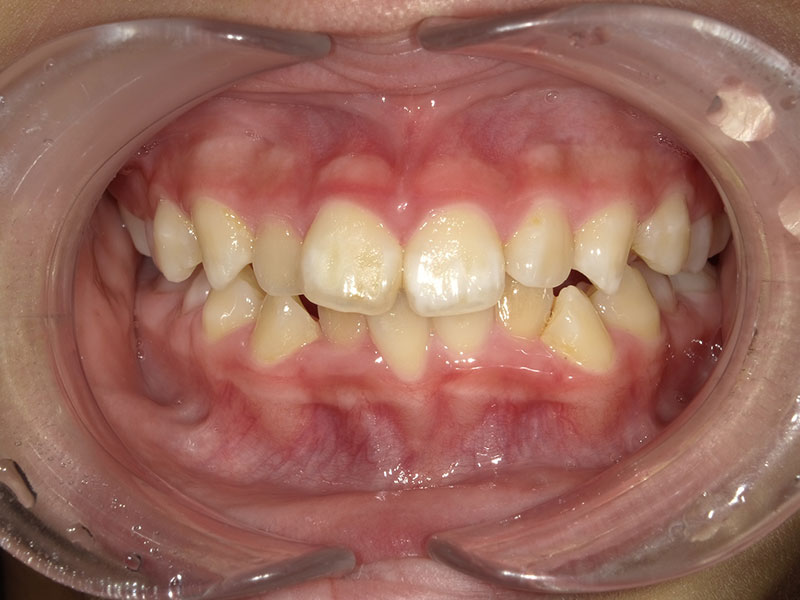

治療前

Before

年齢 43歳

性別 女性

主訴 左下の乳歯を抜きたい